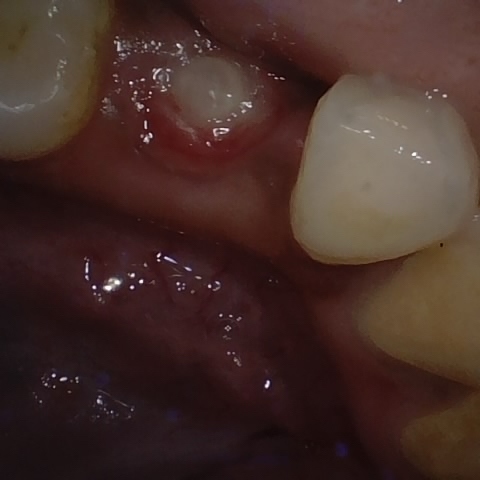

Annotated as "Good"